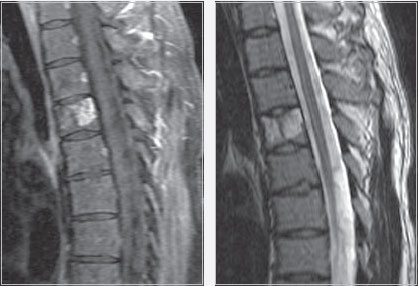

Женщина, 51 год, перелом тела L2-позвонка. Выполнен передний спондилодез L1‐L3. Тело позвонка L2 замещено имплантом Obelisc